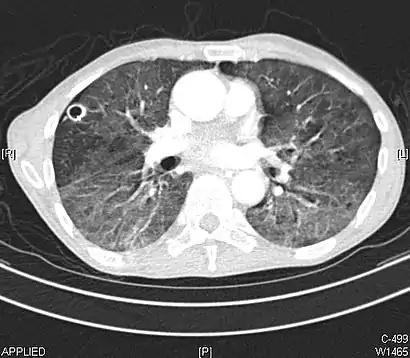

CT image showing ground-glass opacification in the posterior of the right lung (screen left). - Measles

CT image showing diffuse GGOs throughout both lungs. An abscess is also noted in the right lung (screen left). - Adenocarcinoma in situ of the lung